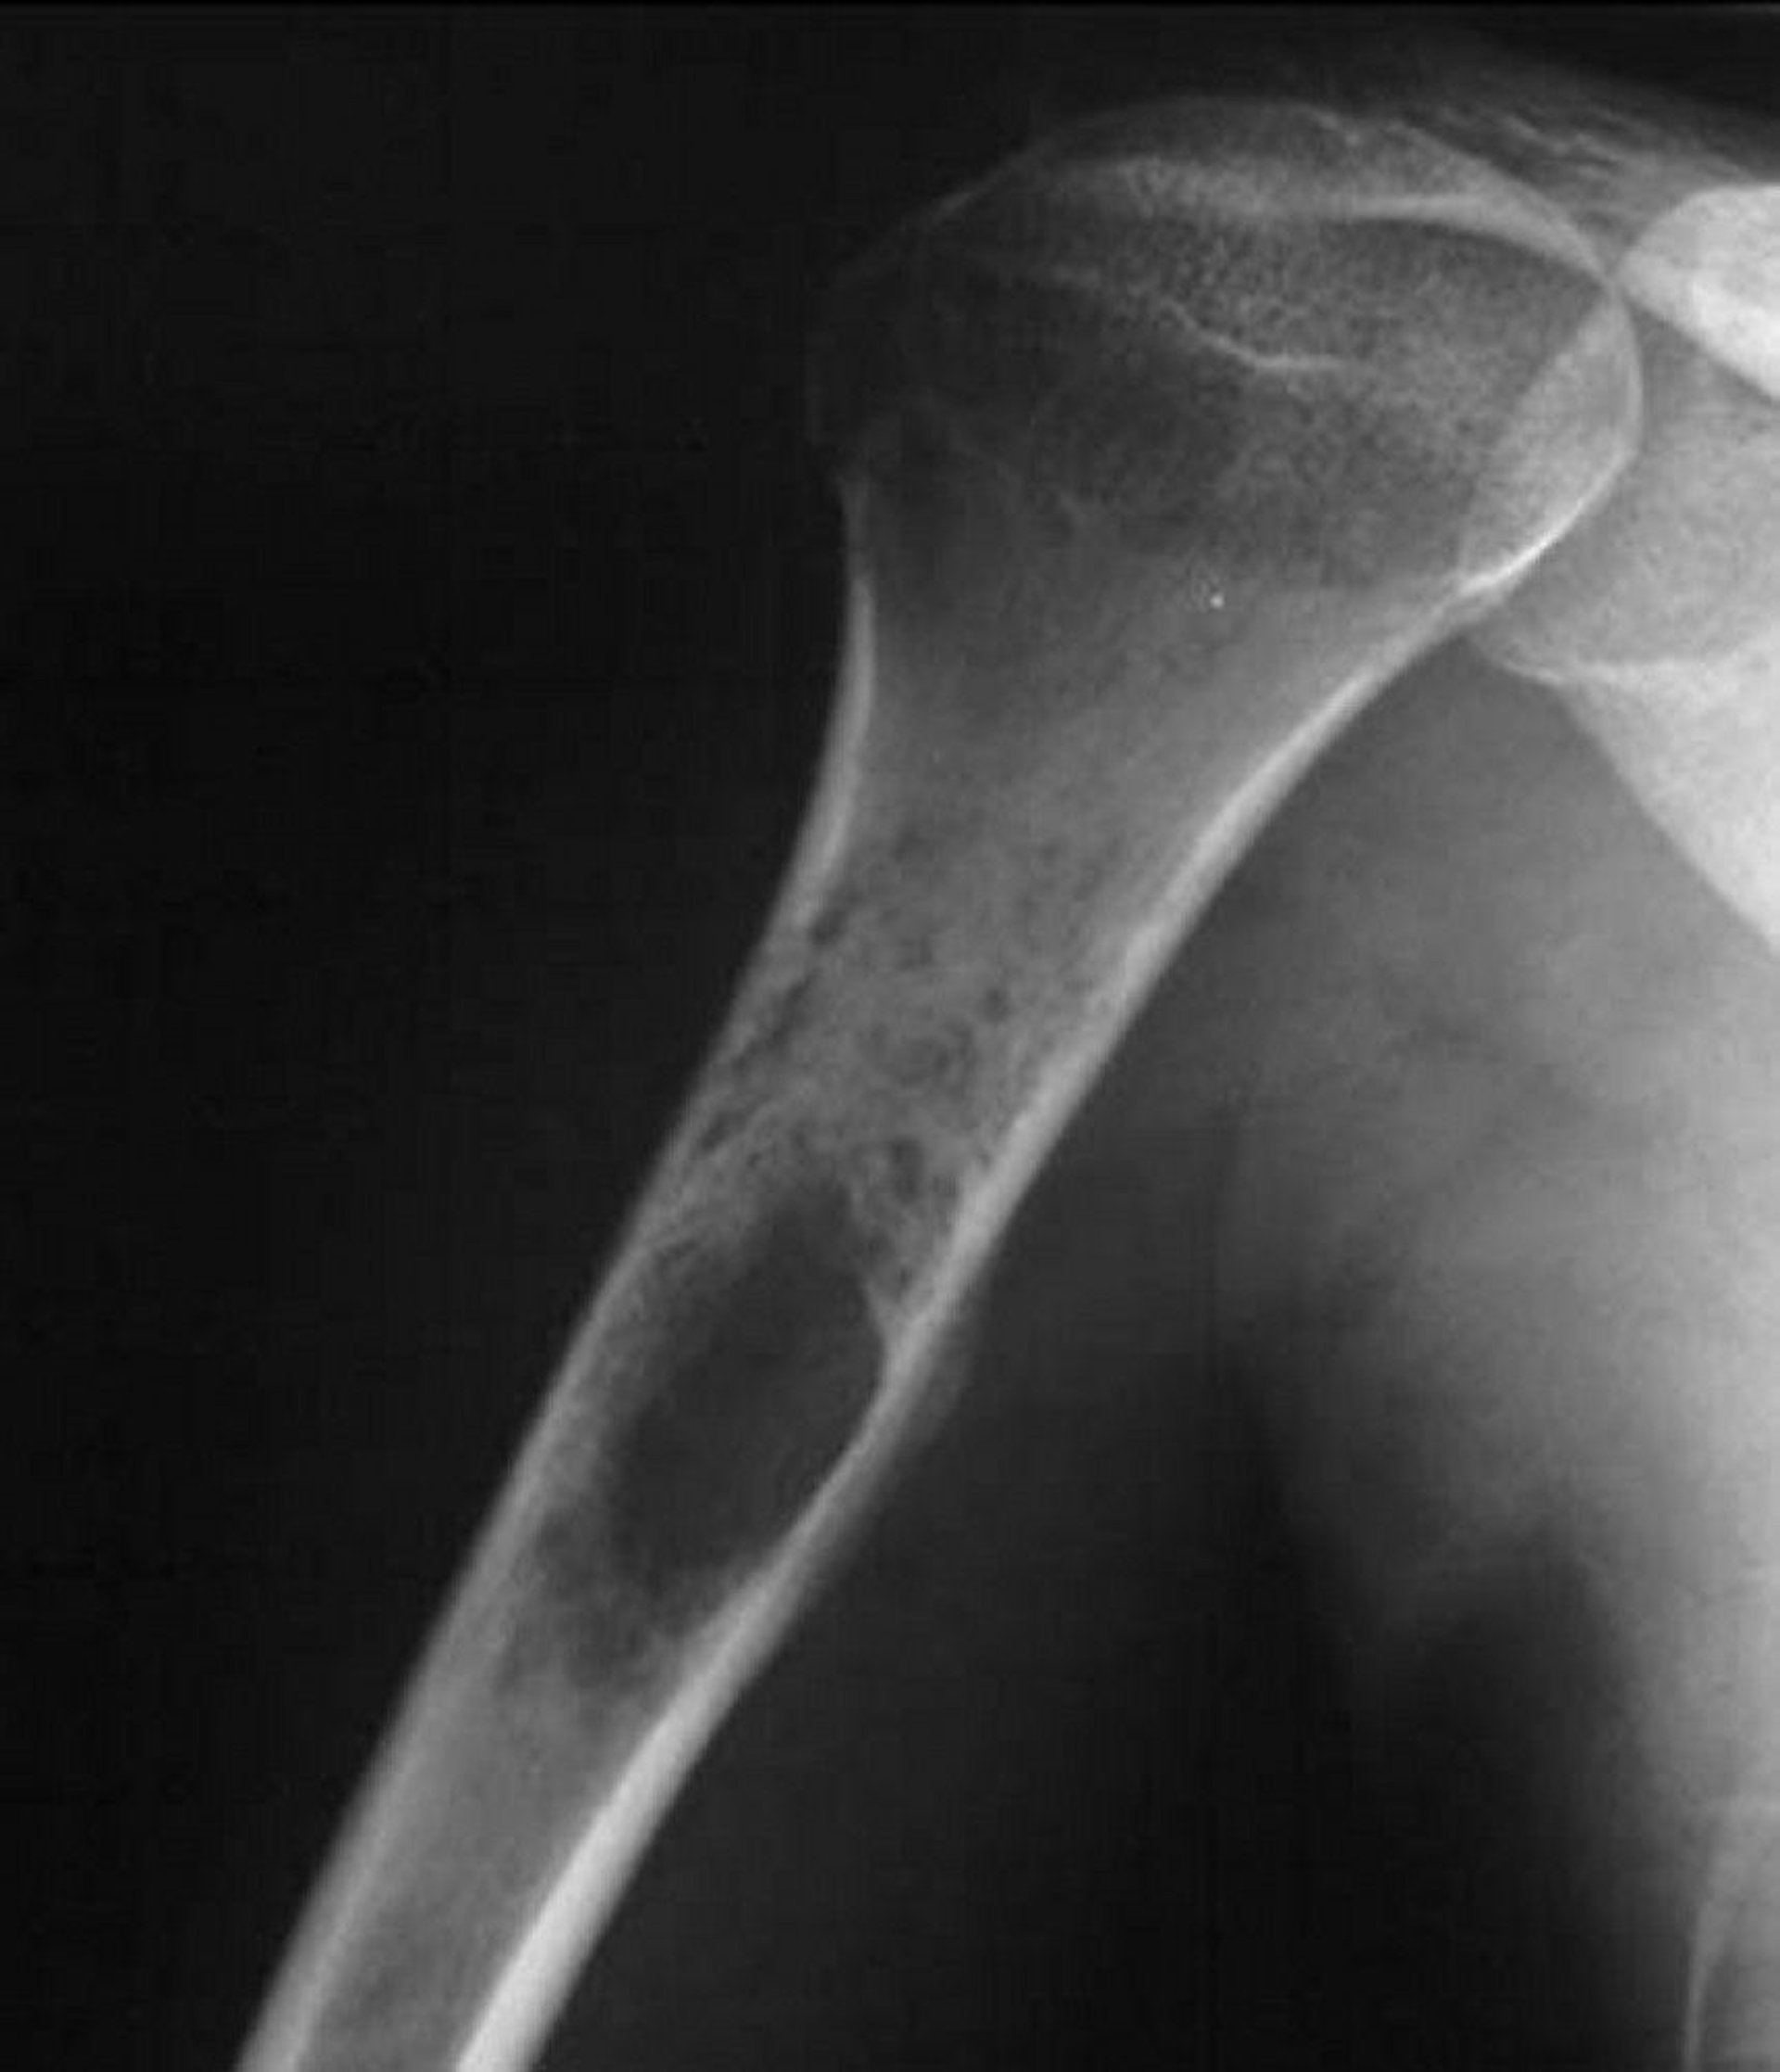

This shoulder radiograph shows a permeative destructive tumor arising in the proximal humerus, which is typical of Ewing sarcoma.

Image courtesy of Michael J. Joyce, MD, and Hakan Ilaslan, MD.